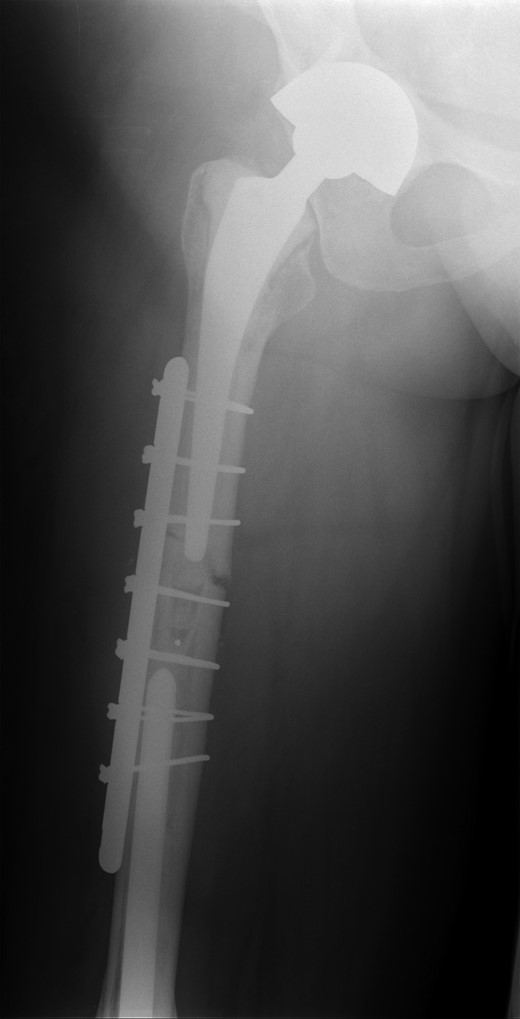

She subsequently sustained a periprosthetic fracture at the distal tip of her right total hip replacement (Fig. 1). An initial attempt was made to manage this fracture with a plate and Dall-Miles cables (Fig. 2); however, the fracture did not unite. The patient went on to have a custom-made cement-linked internal proximal femoral replacement, which had a hollow cylindrical design to accept the stem of the existing well-fixed distal femoral component (Figs 3 and 4). This linked prosthesis effectively converted her separate prostheses to a total femoral replacement, sparing her distal femoral replacement from revision. She had no problems postoperatively and recovered well from her surgery.

Plate and Dall-Miles cable fixation of periprosthetic fracture.